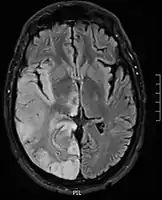

Hemispheric gyriform hyperintense signal variations

Axial fluid-attenuated inversion recovery MRI image demonstrating tumor-related infiltration involving lenticular nuclei (Arrow).

Axial fluid-attenuated inversion recovery MRI image demonstrating tumor-related infiltration involving both temporal lobes (Short arrow), and the substantia nigra (Long arrow).